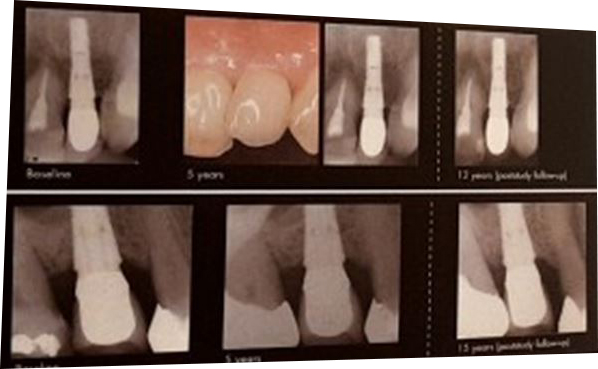

- 아스트라(스웨덴산) 수술 후 12년, 15년 경과되었지만 표면골 손실없음

저희 치과에서 사용중인 '아스트라'는

세계 최초로 미세나사선을 사용한 제품이라

강한 저작압도 효율적으로 분산시킬 수 있습니다.

오래 사용해도 골손실을 최소화 해주죠.

아스트라 임플란트는 수술 후에도

뼈가 거의 녹지 않습니다.

30년 정도의 누적된 자료들을 보면,

녹는 수치가 1년에 0.1mm 미만입니다.

녹지 않는다는 의미이죠.

아스트라 식립후 녹지 않고 유지되는 잇몸뼈